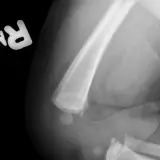

Casos totalmente interativos com as ferramentas que você espera em um PACS — rolagem, ajuste de janela, zoom, movimentação, medidas, ROIs e modo de tela cheia.

Anotações detalhadas destacam os achados principais diretamente nos casos. Clique nos achados vinculados nas descrições dos casos para ir ao local exato no exame.